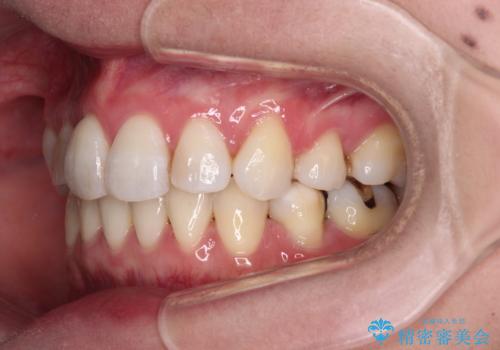

治療期間の目安は3年~3年半でしたが、咬み合わせにより上顎のスペースがなかかな閉じきらず、治療期間が長期化してしまいました。

期間はかかったものの、口元の張り出し感や歯のデコボコが解消され、患者様には大変満足していただけました。